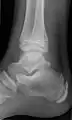

X-ray by dorsoplantar projection, with most common accessory and sesamoid bones of the foot.[16]

BonePrevalence[17]

Sesamoid bones

Sesamoids at the metatarsophalangeal (MTP) joint of the great toeAlways present

Sesamoid of the second metatarsal0.4%

Sesamoid of the third metatarsal0.2%

Sesamoid of the fourth metatarsal0.1%

Sesamoids of the fifth metatarsal4.3%

Sesamoid of the interphalangeal (IP) joint of the great toe2–13%

Ossicles

Os trigonum (not visible in this dorsoplantar projection)7–25%

Os peroneumUp to 26%

Accessory navicular2–21%

Os intermetatarseum1–13%

Os supranaviculare, also called the talonavicular bone1.0–3.5%

Os calcaneus secundarium0.6–7%

Os supratalare0.2–2.4%

Os vesalianum0.1–1%

Os talotibiale 0.5%